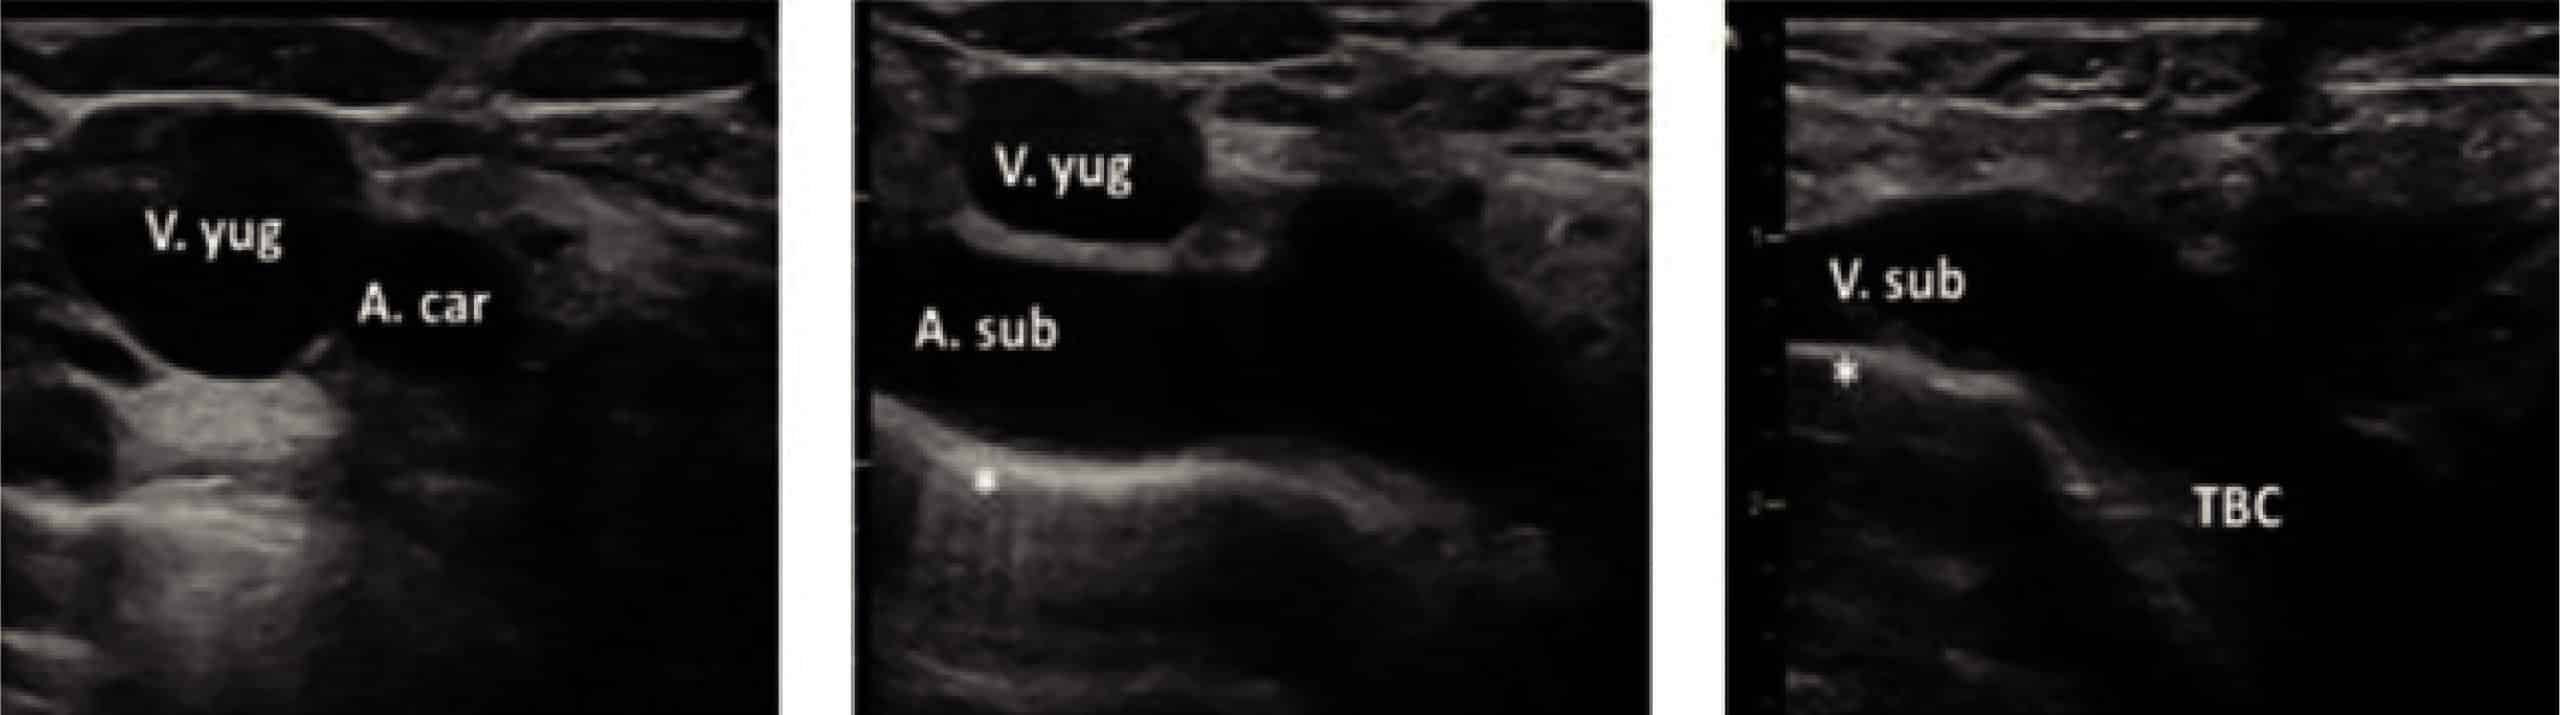

Peculiaridades de los accesos venosos principales: yugular interna, subclavia y braquiocefálica.

Las técnicas ecoguiadas se han convertido en la referencia para el cateterismo de la vena yugular interna (VYI) en niños por las grandes ventajas que aporta. A pesar de que la canalización en el eje corto es la técnica más utilizada por los profesionales, los expertos en la materia advierten que la técnica en eje largo sigue siendo más segura para el paciente y permite la verificación al 100% del emplazamiento correcto del catéter.

La complicación más común de la canalización es la punción accidental de la arteria carótida. Con un examen de prepunción de ultrasonidos (US), la relación anatómica entre la vena y la arteria puede ser investigada para conseguir el mejor plano con la presentación laterolateral de las estructuras y no anteroposterior y, de esta forma, observar el largo de su longitud antes de decidir el mejor punto de perforación. Esto es esencial debido a las posibles variaciones en las relaciones anatómicas.

Vena subclavia y braquiocefálica por abordaje supraclavicular

Un enfoque supraclavicular, es decir, por encima de la clavícula, ofrece una perfecta visualización de la aguja en plano que no se ve interrumpida por estructuras óseas.

Debido a la orientación de la sonda en la fosa supraclavicular visualizaremos sólo el extremo distal de la subclavia y la braquiocefálica. En los niños pequeños y los recién nacidos merece especial atención la identificación del plexo braquial y evitar un enfoque demasiado lateral que pudiera dañarlo.

En cuanto a la vena braquiocefálica, el uso del ecógrafo permite una excelente vista longitudinal de la unión del VYI y VSC para identificar la vena braquiocefálica (VBC) en la región supraclavicular y sin ningún tipo de sombra causada por las estructuras óseas. El abordaje en plano (recomendado por los expertos) ofrece una buena visión tanto de la aguja como de la vena.